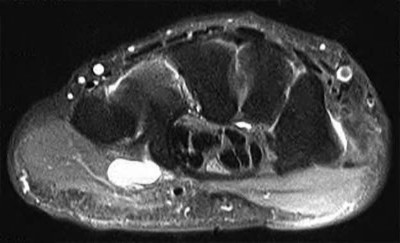

A 35-year-old woman reports wrist pain after a fall onto an outstretched hand. On exam, she has focal tenderness over the wrist snuffbox. A radiograph and CT image are shown in Figures A and B. What is the proper treatment of her injury?